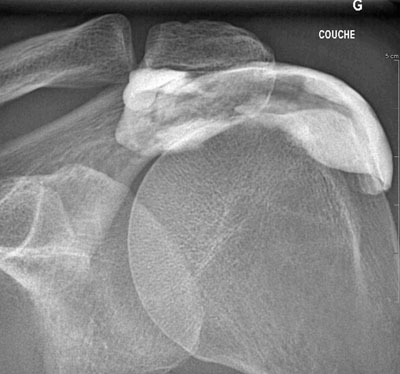

Radiographie de l'épaule. L'épaule a 2 articulations : l'articulation acromio-claviculaire (flèche pleine) et l'articulation omo-humérale (flèche creuse).

Infiltration de l'articulation acromio-claviculaire (épaule).